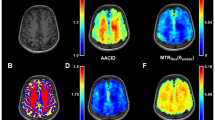

An example of the APT effect visualized with different metrics across two sessions can be seen in Fig. 3. From visual inspection, LD and MTRasym consistently showed hyperintensity in the region of (enhancing) tumor compared with contralateral healthy tissue across two scan sessions, while for MTRREX hypointensity can be observed consistently in the tumor ROI compared with healthy tissue.

Example slice of patient 4 (recurrent glioblastoma in parieto-occipital lobe) showing from left to right, post contrast T1-weighted, LD APT, MTRasym APT, and MTRREX APT images from scan 1.a.1 and scan 2.a.1 (Fig. 1) to illustrate between-session reproducibility.